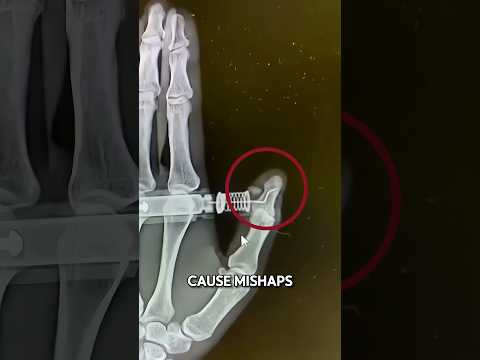

When an EpiPen Goes Wrong

EpiPen Gone Wrong ⚠️

Doctor Reacts: EpiPen fail

EpiPen Gone Wrong 😨

The EpiPen Mistake That Sent Her to the ER! 🚑💉⚠️